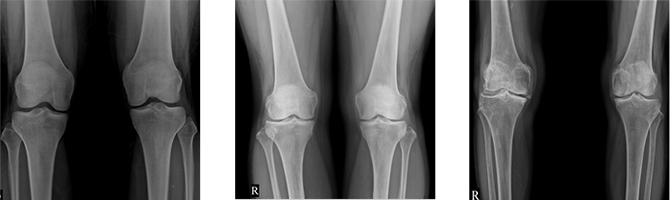

Osteoarthritis Diagnosis

Osteoarthritis can be relatively easily diagnosed using X-rays. However, in elderly patients, some degree of degenerative changes are a natural occurrence, so diagnosis should be made by combining medical history and physical examinations. Additionally, depending on the severity and duration of symptoms, ultrasound, MRI, and blood tests may be required.

• Normal X-ray

Findings

• Early-stage Osteoarthritis

X-ray Findings

• Advanced-stage Osteoarthritis